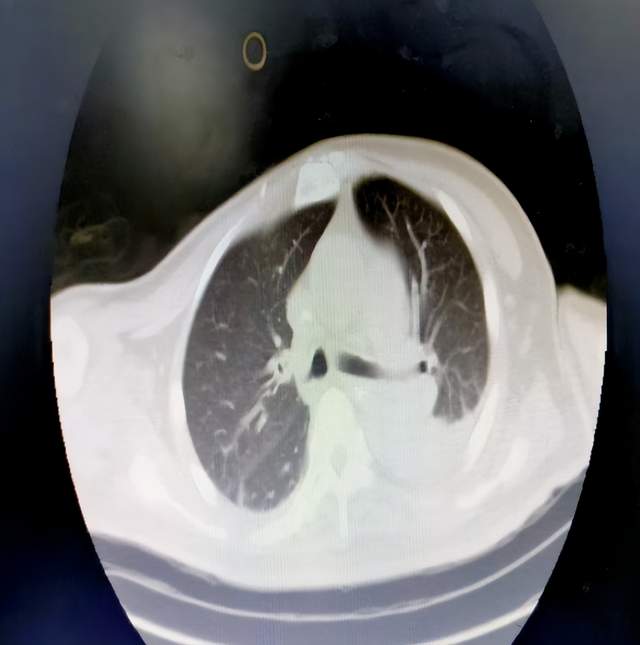

目前该项技术已为众多患者带来显著疗效,一位因自发性脑出血入院治疗的老年男性患者,在持续有创呼吸机辅助呼吸一周后出现双下肺坠积,经过应用手法膨肺联合纤支镜治疗后,患者病情取得明显改善。